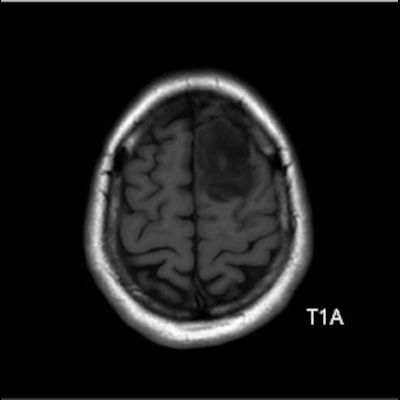

- Sol frontal kortikal-subkortikal yerleşimli aksiyel T2A görüntüde hiperintens sinyal özelliği gösteren (oklar) ve FLAIR görüntüde sinyali ağırlıklı olarak baskılanan (oklar) kitlesel lezyon izleniyor. Lezyon T1A görüntüde hipointens olup post-kontrast T1A görüntüde bu düzeyde patolojik kontrastlanma izlenmiyor (oklar).

- T1AG’de genellikle hipointens, T2AG’de ise genellikle homojen hiperintens görünümde ve kitle etkisi hafif-orta düzeydedir.Ödem genellikle eşlik etmez ya da minimal düzeydedir.

- Grade 2 ve 3 tümörlerde çoğunlukla kontrast tutulumu yoktur veya minimal düzeydedir. Grade 4 IDH-mutant astrositomlarda, nekroz veya mikrovasküler proliferasyon varsa heterojen kontrast tutulum gözlenebilir. Kontrast tutulumu her zaman malignite derecesini yansıtmayabilir; bu nedenle biyopsi ve moleküler analiz mutlaka gereklidir.